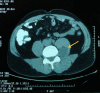

Case presentation: We report a case of a mass located in the L5 lumbar spine in a 42 year old man, presented with intermittent lumbar pain. Ultrasound, CT and MRI were used to examine the characteristics of the lesion. Fine needle aspiration showed cytologic characteristics of benign schwannoma and final histological diagnosis was ancient schwannoma. An extraperitoneal approach, through a left paramedian incision was used to approach the site of the mass. The lesion originated from the nerve root of the L4-L5 lumbar spinal space and a complete excision was achieved.